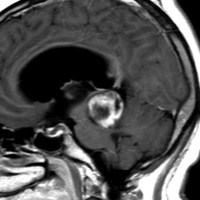

19歳で偶然見つかった例

頭部打撲で検査され偶然発見された19歳男性ものです。中脳視蓋全体が腫大して腫瘍化しています。左側にのう胞があり周囲が淡くガドリニウムで増強されます。

中脳水道の癒着閉塞により,高度の停止性水頭症になっています。高身長ですが頭囲が61cmありました。小さい頃から頭が大きいので家族も気にならないようです。数年以上あるいは10年近くの長期にわたってこの水頭症は変わらないのでしょう。

頭痛などの症状はなく,眼底所見も視神経乳頭の異常はありませんでした。無治療で経過観察をしています。認知機能も全く正常で,国立大学から大学院に進む予定です。